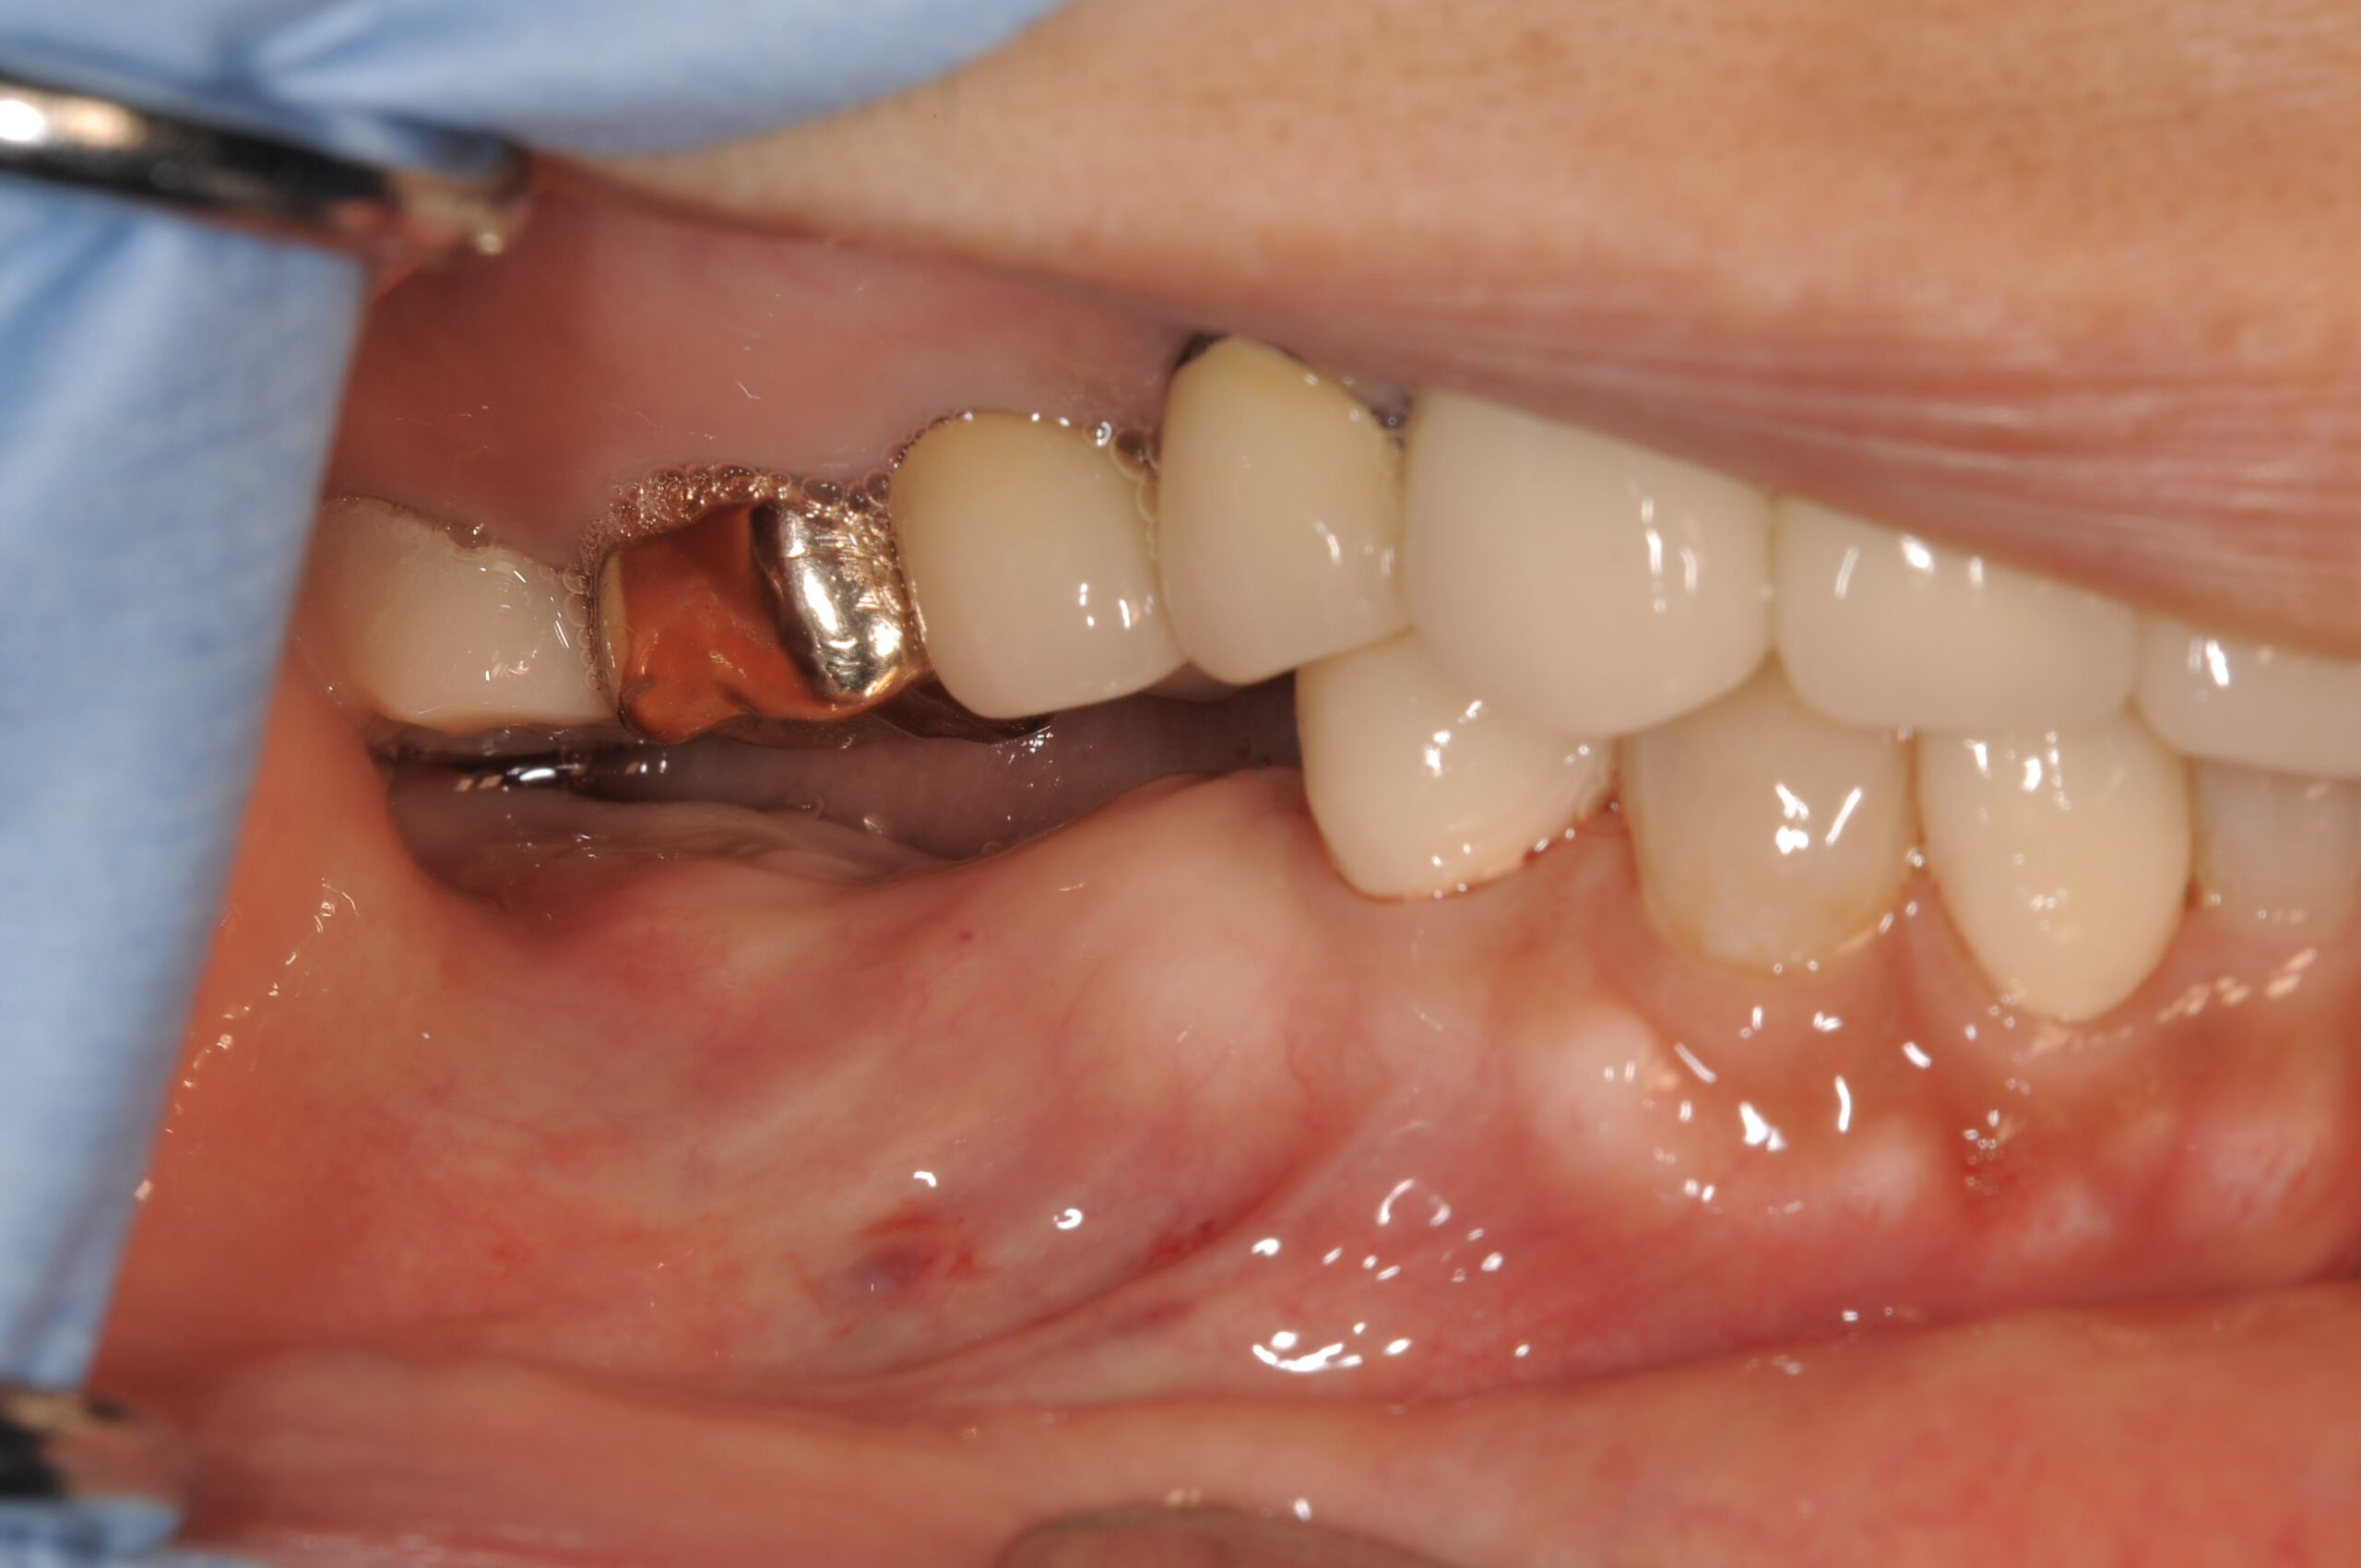

骨の固さはClass2~3で標準的、幅も深さも十分にありますが、嚙合わさる上の奥歯との間の隙間が狭く、歯を作るのに苦労しそうなケースでした。

右下の5,7部位のインプラントブリッジ予定ですが、ワーキングスペースが少ないです。